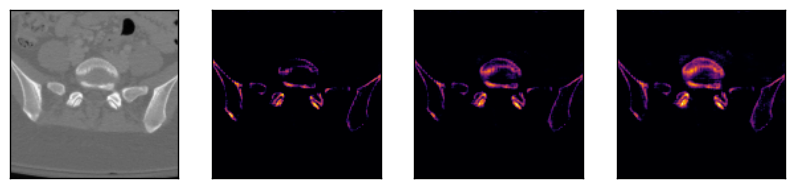

Some segmentation results at different vertebrae (top) and liver (bottom) areas are depicted in Fig. 2. The red contour corresponds to the outline of the prediction, green to the ground-truth and yellow to the overlap of the outlines.

IV-E Visual feature inspection

In order to visually demonstrate the sequential nature of the features learnt by our model, we performed the following test. We passed two sequences to the network (both for vertebrae), each containing three identical slices (first column in Fig. 3). The columns show some of the features extracted after the penultimate upsampling step (after layer in Table I) before passing them to the final bidirectional C-LSTM block. The visualization shows that the layers respond differently to the same input element, activating different parts of the organ of interest. The brighter colour intensities correspond to higher activations. Comparing the rows, it shows that the network is able to learn spatial correlations in both directions.